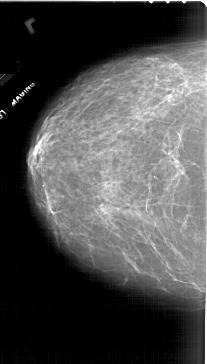

A_1745_1.LEFT_CC

LEFT_CC LINES 6541 PIXELS_PER_LINE 3721 BITS_PER_PIXEL 12 RESOLUTION 43.5 NON_OVERLAY